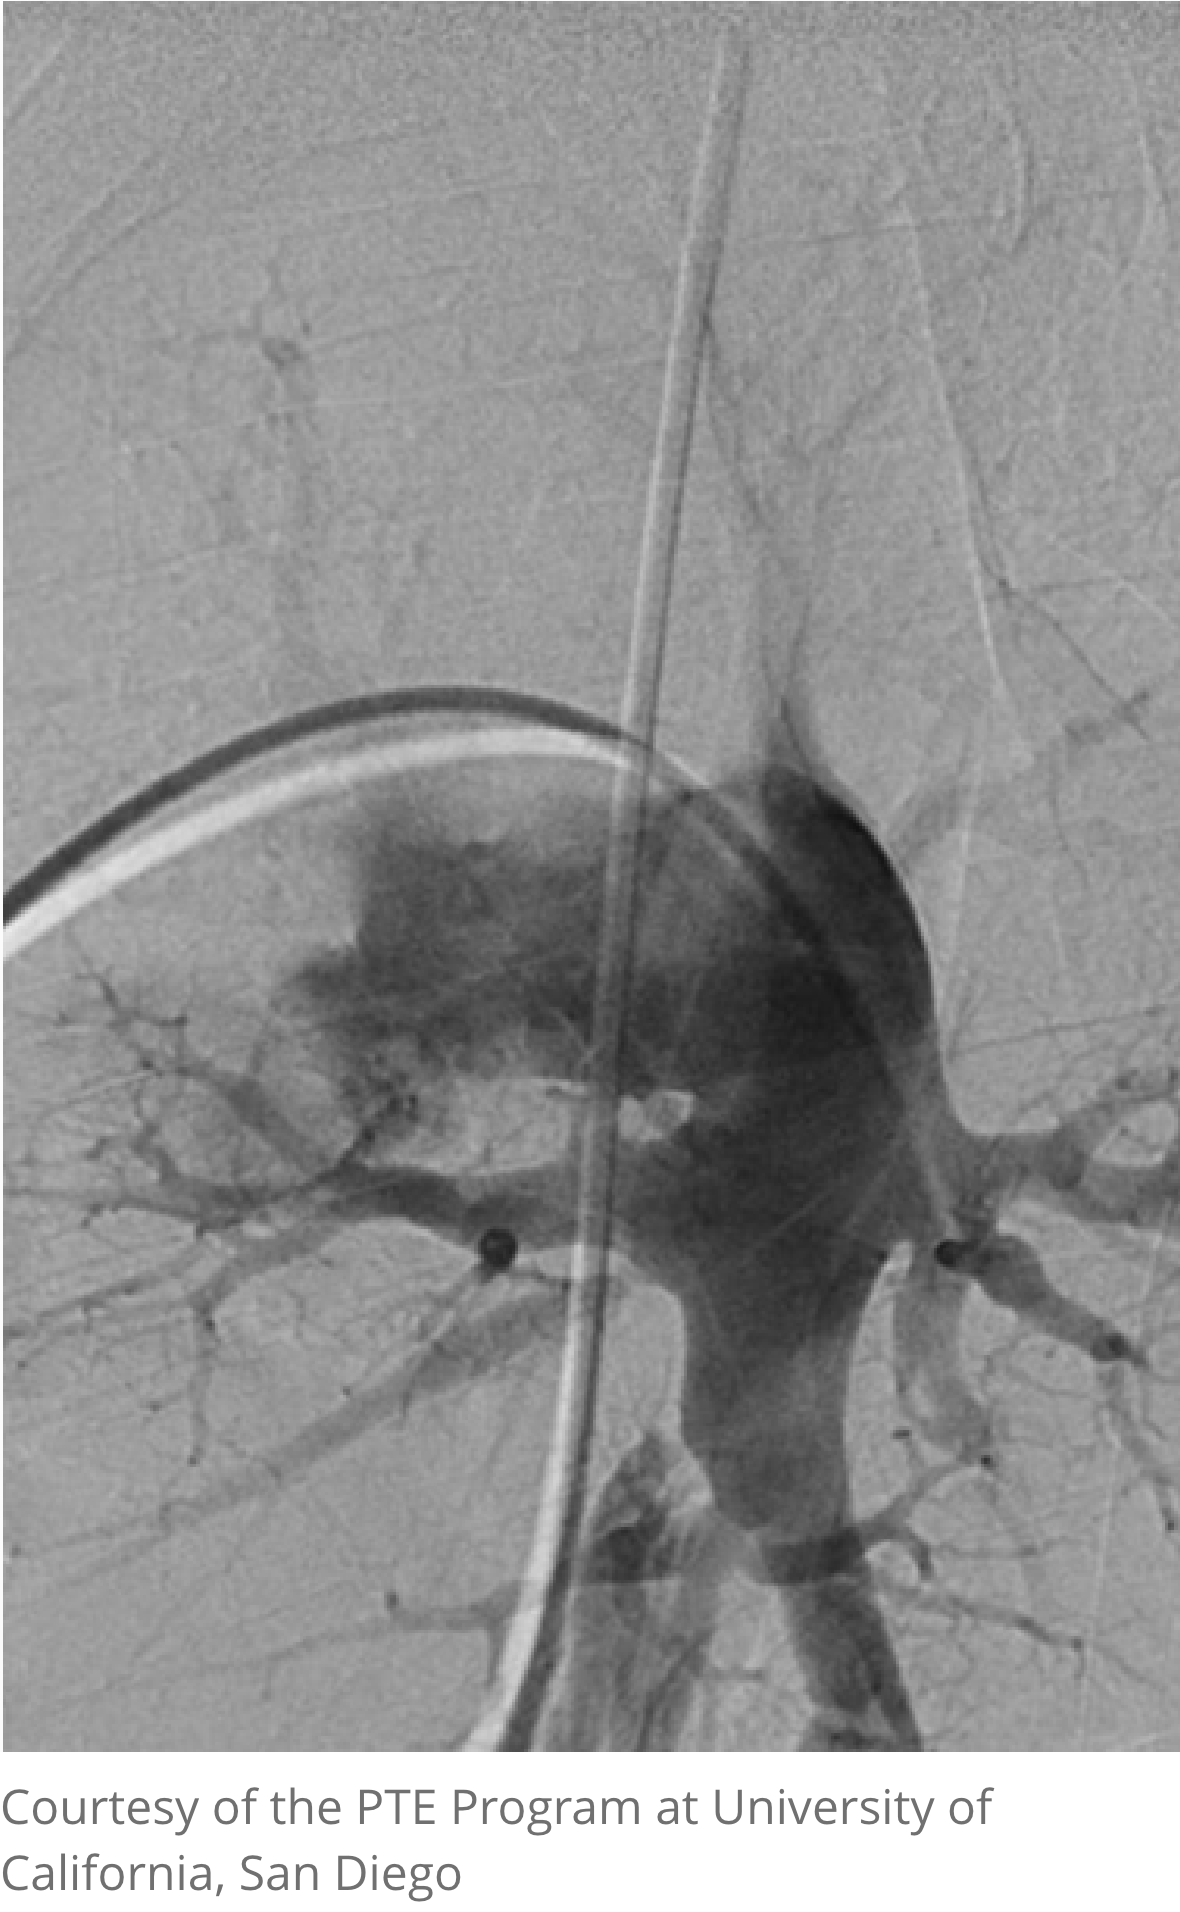

Pulmonary angiography

Pulmonary angiography (digital subtraction angiography) is used to assess treatment options when computed tomography pulmonary angiogram (CTPA) is inconclusive3

- Defines extent and distribution of disease and helps distinguish operable from inoperable disease4

- Combined with right heart catheterization (RHC), a correlation can be made between degree of disease and degree of hemodynamic impairment1,2

- The procedure should always be carried out by experienced staff at a unit with specialist pulmonary hypertension (PH) experience, preferably the unit at which PTE surgery would be performed1,2